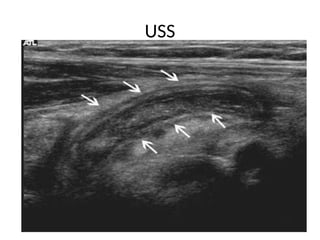

• Ultrasound

– 75 to 90 % sensitive, 86 to 100 % specific

– Noninvasive, low cost, but operator-dependent

– Good for diagnosing GYN disorders

USS